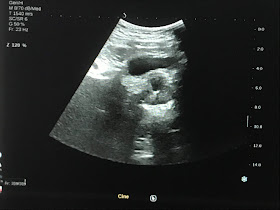

US SCAN

US 1:  ONE MASS  NEAR LEFT SITE OF  UMBILICUS  WITH  SANDWICH SIGN.

US 2: MANY LYMPH NODES HYPOECHOIC,  SIZE 2-3 CM  WITH STRUCTURE CHANGE AND NO HILUS.

US 3: SAME  STRUCTURE  OF LYMPH NODE IN MESENTERIUM.